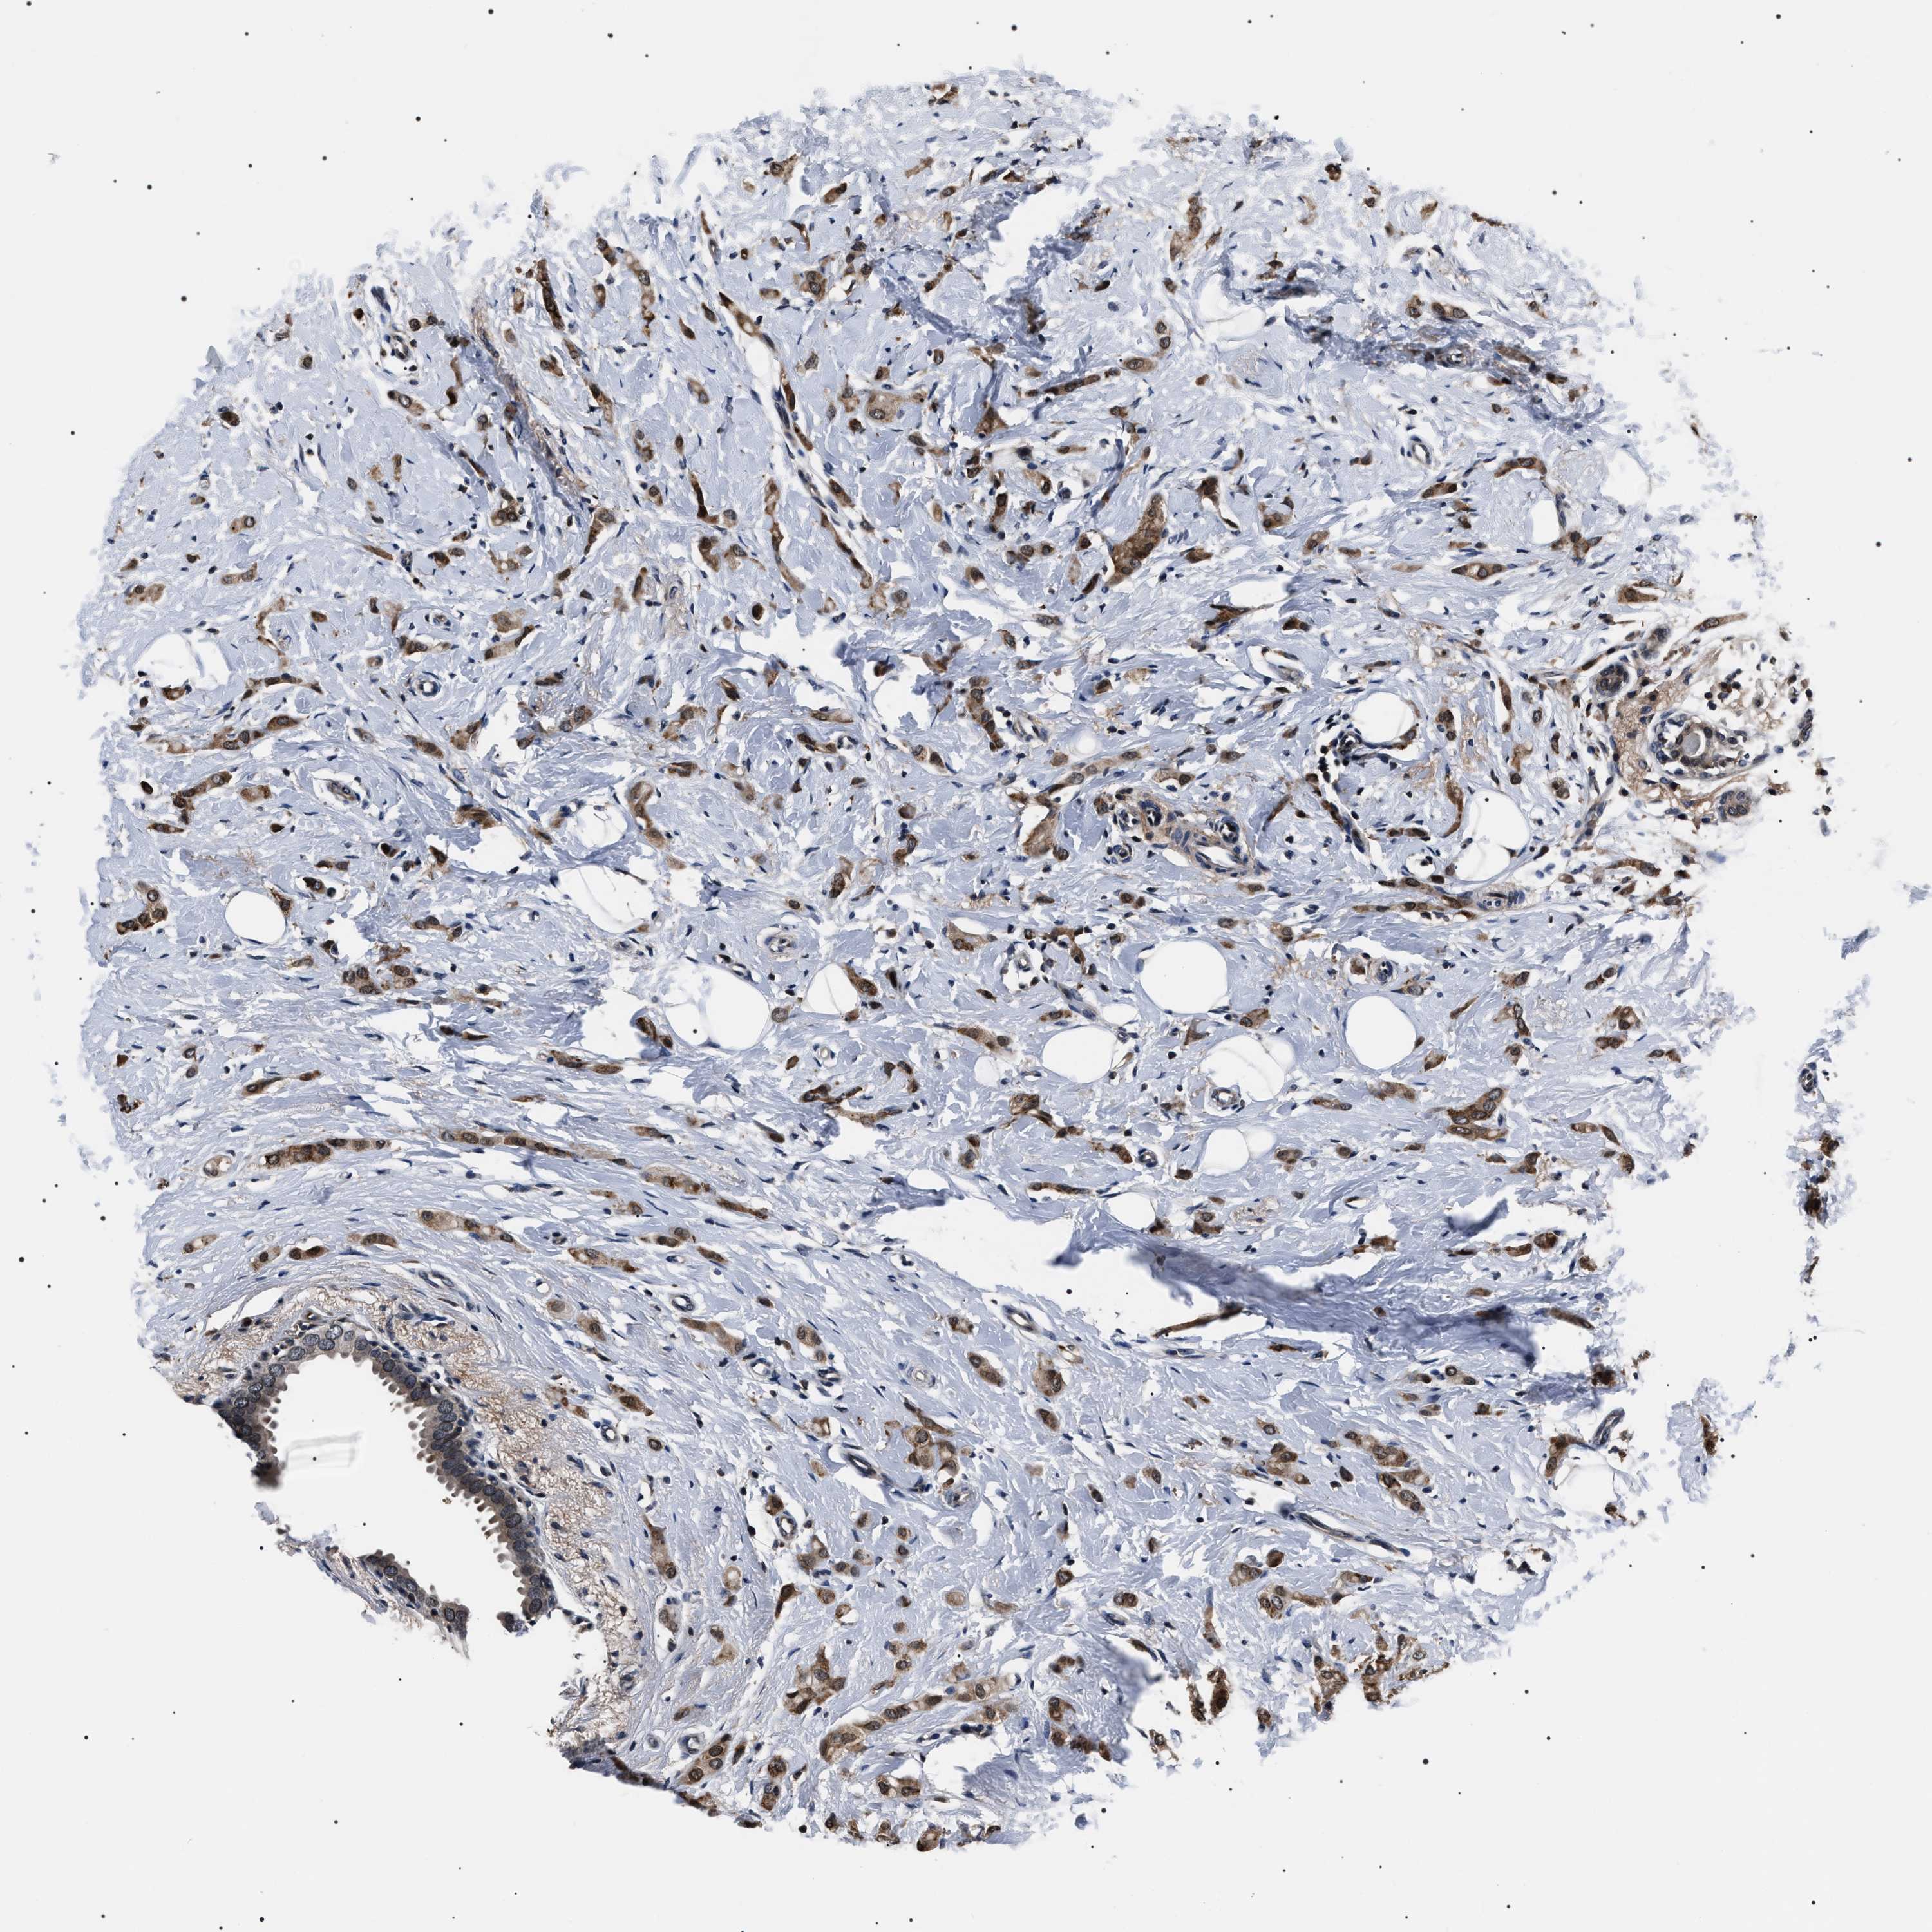

CANCER BREAST CANCER Show tissue menu

BRCA TCGA BRCA VALIDATION PROTEIN EXPRESSION

ANTIBODIES

AND

VALIDATION